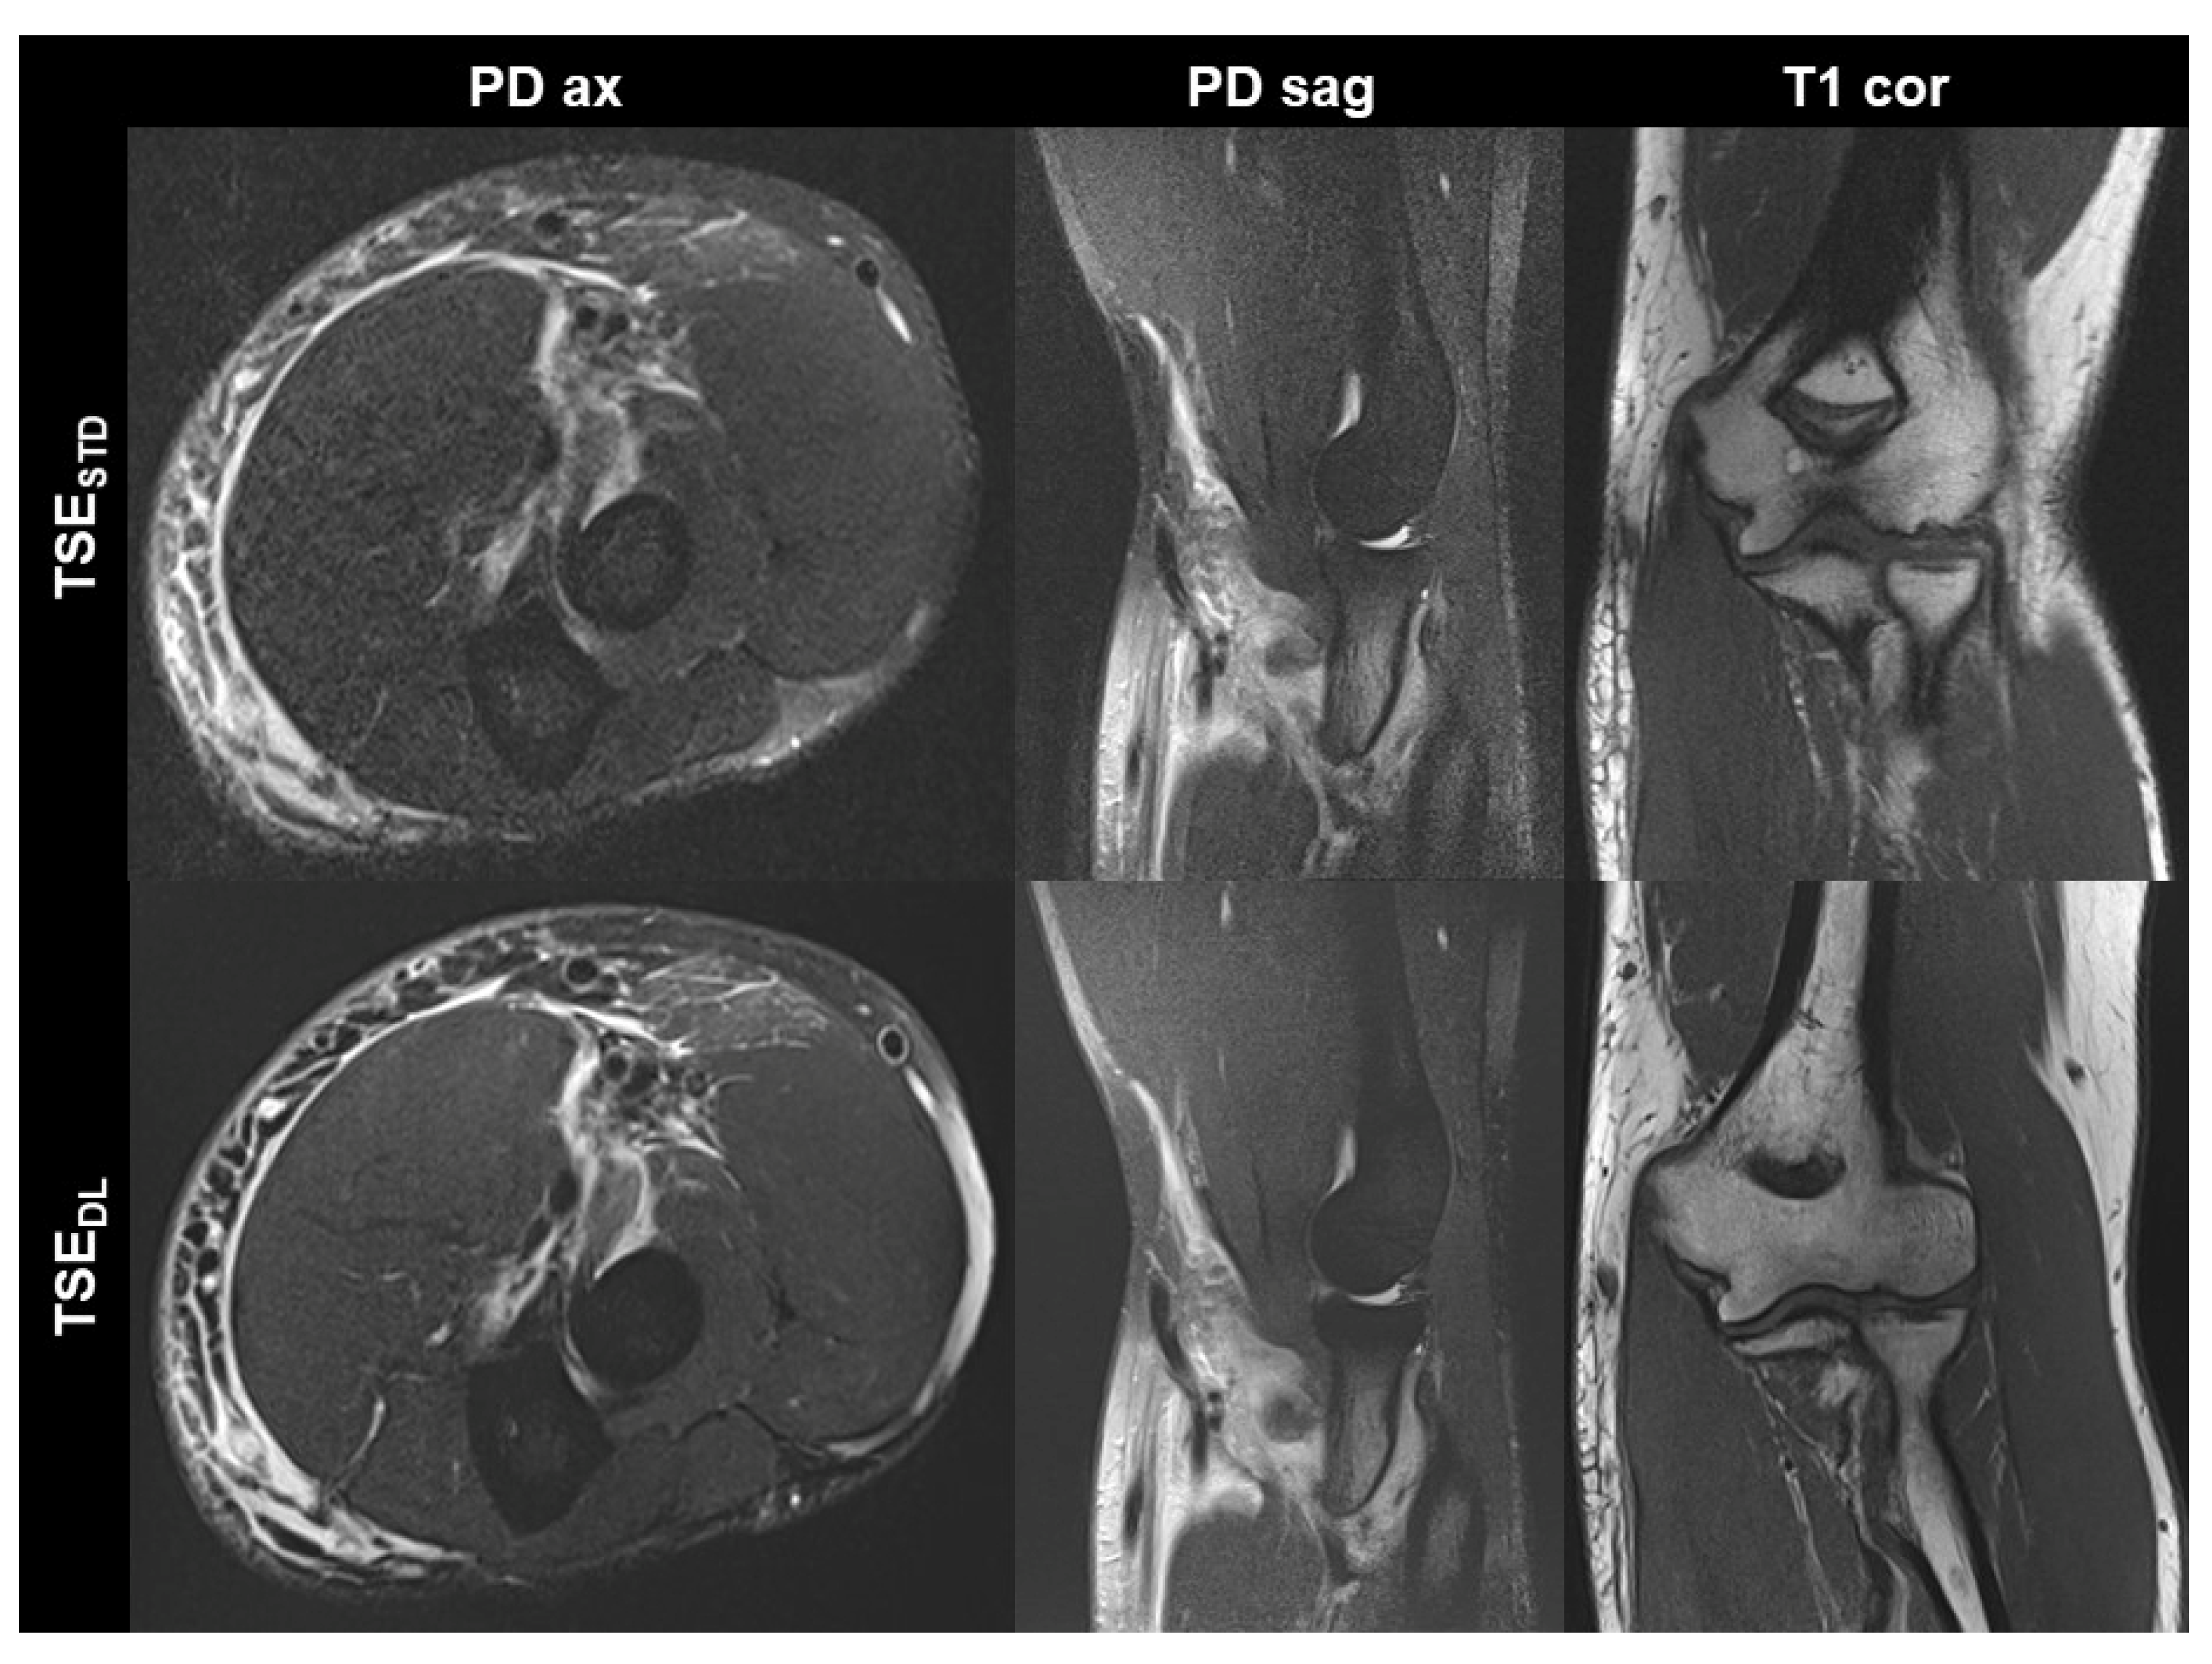

TSEDL was successfully performed in each of the 17 included participants (mean age 43 ± 16 (20–70), years, eight men). Seven exams were performed at 1.5 T and 10 exams at 3 T. TSEDL enabled a scan time reduction by more than 35% at 1.5 T (TSEDL 8:19 min vs. TSESTD 13:06 min) and by more than 55% at 3 T (TSEDL 6:48 min vs. TSESTD 15:15 min). Image examples with comparisons of TSESTD and TSEDL are displayed in Figure 1, Figure 2, Figure 3 and Figure 4.

Figure 3. Elbow MRI acquired at 1.5 T in a 36-year-old male patient with clinically suspected biceps tendon tear after trauma with the institution’s standard turbo spin echo (TSE) sequences (TSESTD, upper row) and deep learning-reconstructed TSE sequences (TSEDL, lower row). The MRI examination confirmed the suspicion of a partial tear of the biceps’ tendon at its insertion with a peritendinous hematoma. Noise is reduced in the DL-reconstructed axial and sagittal fat-suppressed PD-weighted images (PD ax and PD sag). The intact ulnar collateral ligament is depicted well in the standard and DL-reconstructed coronal T1-weighted images; the difference in angulation between the two images is due to movement between acquisitions.